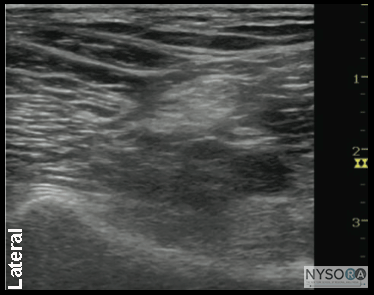

General Considerations Performance of a sciatic block above the popliteal fossa benefits from ultrasound guidance in several ways. The anatomy of the sciatic nerve as it approaches the popliteal fossa can be variable, and the division into the tibial nerve (TN) and common peroneal nerve (CPN) occurs at a variable distance from the crease. Knowledge of the location of the TPN and CPN in relation to each other is beneficial in ensuring the anesthesia of both divisions of the sciatic nerve. Moreover, with nerve stimulator-based techniques, larger volumes (e.g., >40 mL) of local anesthetic often are required to increase the chance of block success and rapid onset. A reduction in local anesthetic volume can be achieved with ultrasound guidance because the injection can be halted once adequate spread is documented. The two approaches to the popliteal sciatic block common in our practice are the lateral approach with patient in supine (more commonly, oblique position) and the posterior approach (Figure 2). It should be noted that with the lateral approach, the resulting ultrasound image is identical to the image in the posterior approach. Both are discussed in this chapter. Only the patient position and needle path differ between the two approaches; the rest of the technique details are essentially the same. Ultrasound Anatomy With the posterior and the lateral approaches, the transducer position is identical; thus the sonographic anatomy appears the same. However, note that although the image appears the same, there is a 180° difference in patient orientation. Beginning with the transducer in the transverse position at the popliteal crease, the popliteal artery is identified, aided with the color Doppler ultrasound when necessary, at a depth of approximately 3 to 4 cm. The popliteal vein accompanies the artery. On either side of the artery are the biceps femoris muscles (lateral) and the semimembranosus and semitendinosus muscles (medial). Superficial (i.e., toward the skin surface) and lateral to the artery is the tibial nerve, seen as a hyperechoic, oval, or round structure with a stippled or honeycomb pattern on the interior (Figure 3A and B). If difficulty in identifying the nerve is encountered, the patient can be asked to dorsiflex and plantar flex the ankle, which makes the nerve rotate or move in relation to its surroundings. Once the tibial nerve is identified, an attempt can be made to visualize the common peroneal nerve, which is located even more superficial and lateral to the tibial nerve. The transducer should be slid proximally until the tibial and peroneal nerves are visualized coming together to form the sciatic nerve before its division. (Figure 4A and B). This junction usually occurs at a distance between 5 and 10 cm from the popliteal crease but this may occur very close to the crease or (less commonly) more proximally in the thigh. As the transducer is moved proximally, the popliteal vessels move anteriorly (i.e., deeper) and therefore become less visible. Adjustments in depth, gain, and direction of the ultrasound beam should be made to keep the nerve visible at all times. The sciatic nerve typically is visualized at a depth of 2 to 4 cm.